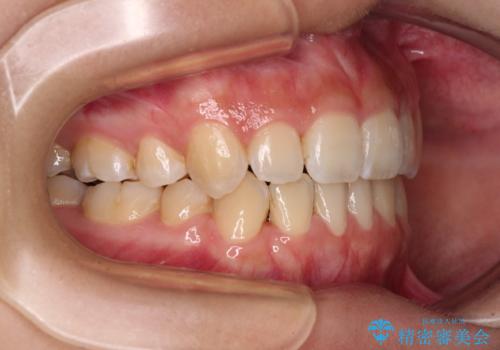

デコボコと八重歯の目立つ前歯 ワイヤー装置による抜歯矯正

- 上下前歯のデコボコと八重歯を気にして来院された患者様です。

叢生を解消する際に出っ歯とならないようにするために、上下左右の小臼歯計4本を抜歯することとしました。